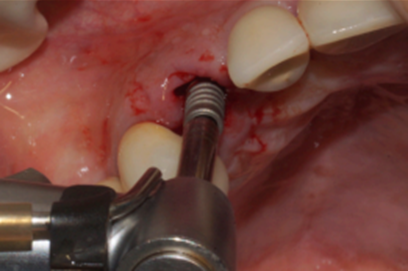

Uma vez selecionado, o pilar Ideale foi instalado e torqueado a 20 Ncm como recomendado pelo fabricante (Figura 12). Nessa mesma consulta foi colocado sobre o pilar Ideale um transferente digital referente ao mesmo e as arcadas foram escaneadas (Figuras 13, 14 e 15).

Figura 12 – Pilar Ideale de 3.3 X 4.0 X 1.5 de 17° instalado